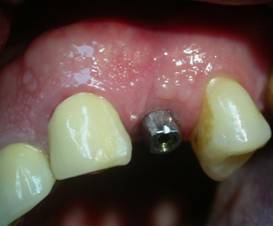

A distanza di 8 giorni dall’intervento, sono stati rimossi i punti di sutura dal lembo mucoso, in cui emerge l’esposizione della vite tappo crestale, contornato da buona gengiva aderente, che potrà continuare a guarire per seconda intenzione, si consiglia il mantenimento quotidiano della Igiene Orale con Antibatterico spray di Clorexidina gluconato (0,2%) e gel di Aminogam (Errekappa Euroterapici) quale coadiuvante nei processi di rigenerazione della mucosa orale.